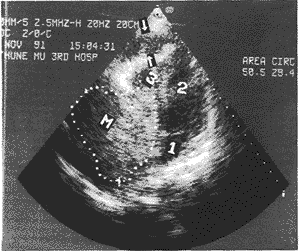

3、超聲心動圖:M型超聲在心前壁之間和心後壁之後均見有液性暗區,即當心包膜和心外膜之間最大舒張期暗區(10毫米時,則積液為小量;如在10-19毫米之間則為中等量;如大於20毫米,則為大量)。

並發本病的前提是由於心包積液內含有膿性細胞,當發生感染型心內膜炎時,由於瓣膜受累,滲出的纖維蛋白和白細胞以及細菌可以形成贅生物,附著於受累的瓣膜上,在超聲心動圖檢查時,這種贅生物所形成的反射回聲,是超聲心動圖的特徵性表現,在二維超聲上,還可以清楚的看見贅生物的大小、形態、附著位置、活動情況,故贅生物的檢出對超聲診斷感染性心內膜炎幫助極大。